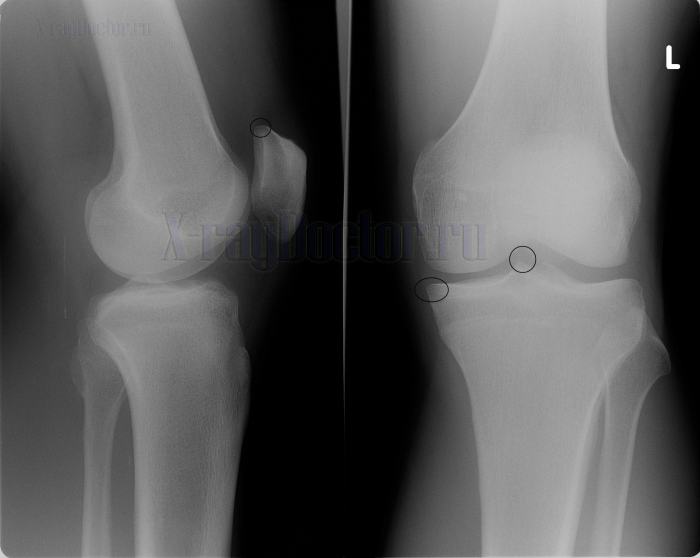

Рентгеновский снимок при гонартрозе

Протокол описания: На представленной рентгенограмме коленного сустава в прямой и боковой проекциях визуализируется сужение